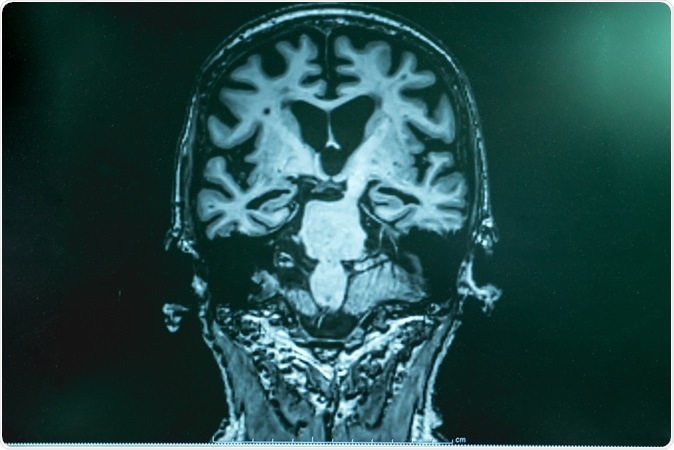

Alzheimer's disease with MRI. Image Credit: Atthapon Raksthaput ./ Shutterstock